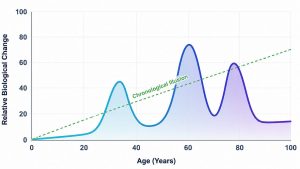

Durazzo explained that increased lifetime alcohol consumption and older age were linked to diminished blood flow and thinner cortex across most brain regions studied, highlighting a concerning connection. Specifically, in 68% of measured regions, higher lifetime drinking correlated with reduced blood flow. This was especially noticeable in the frontal, parietal, and occipital lobes.

The interplay of aging and alcohol intake remarkably impacted the brain’s blood flow, with nearly half of the studied regions reflecting this pattern. “We were surprised by how strong the correlations were between drinking history and decreasing blood flow,” Durazzo added.

Similar trends were found regarding the brain’s structure. Increased lifetime consumption was associated with a thinner cerebral cortex in various regions, notably the frontal and parietal lobes, which are critical for executive functioning and sensory processing. These areas might be particularly susceptible to damage from alcohol over time.

A thinner cortex could suggest changes at the cellular level, possibly due to oxidative stress, which occurs when unstable molecules harm cells. Alcohol can elevate oxidative stress, and aging generally exacerbates this issue. This combined effect might account for the connection between age, drinking, and diminished brain health.